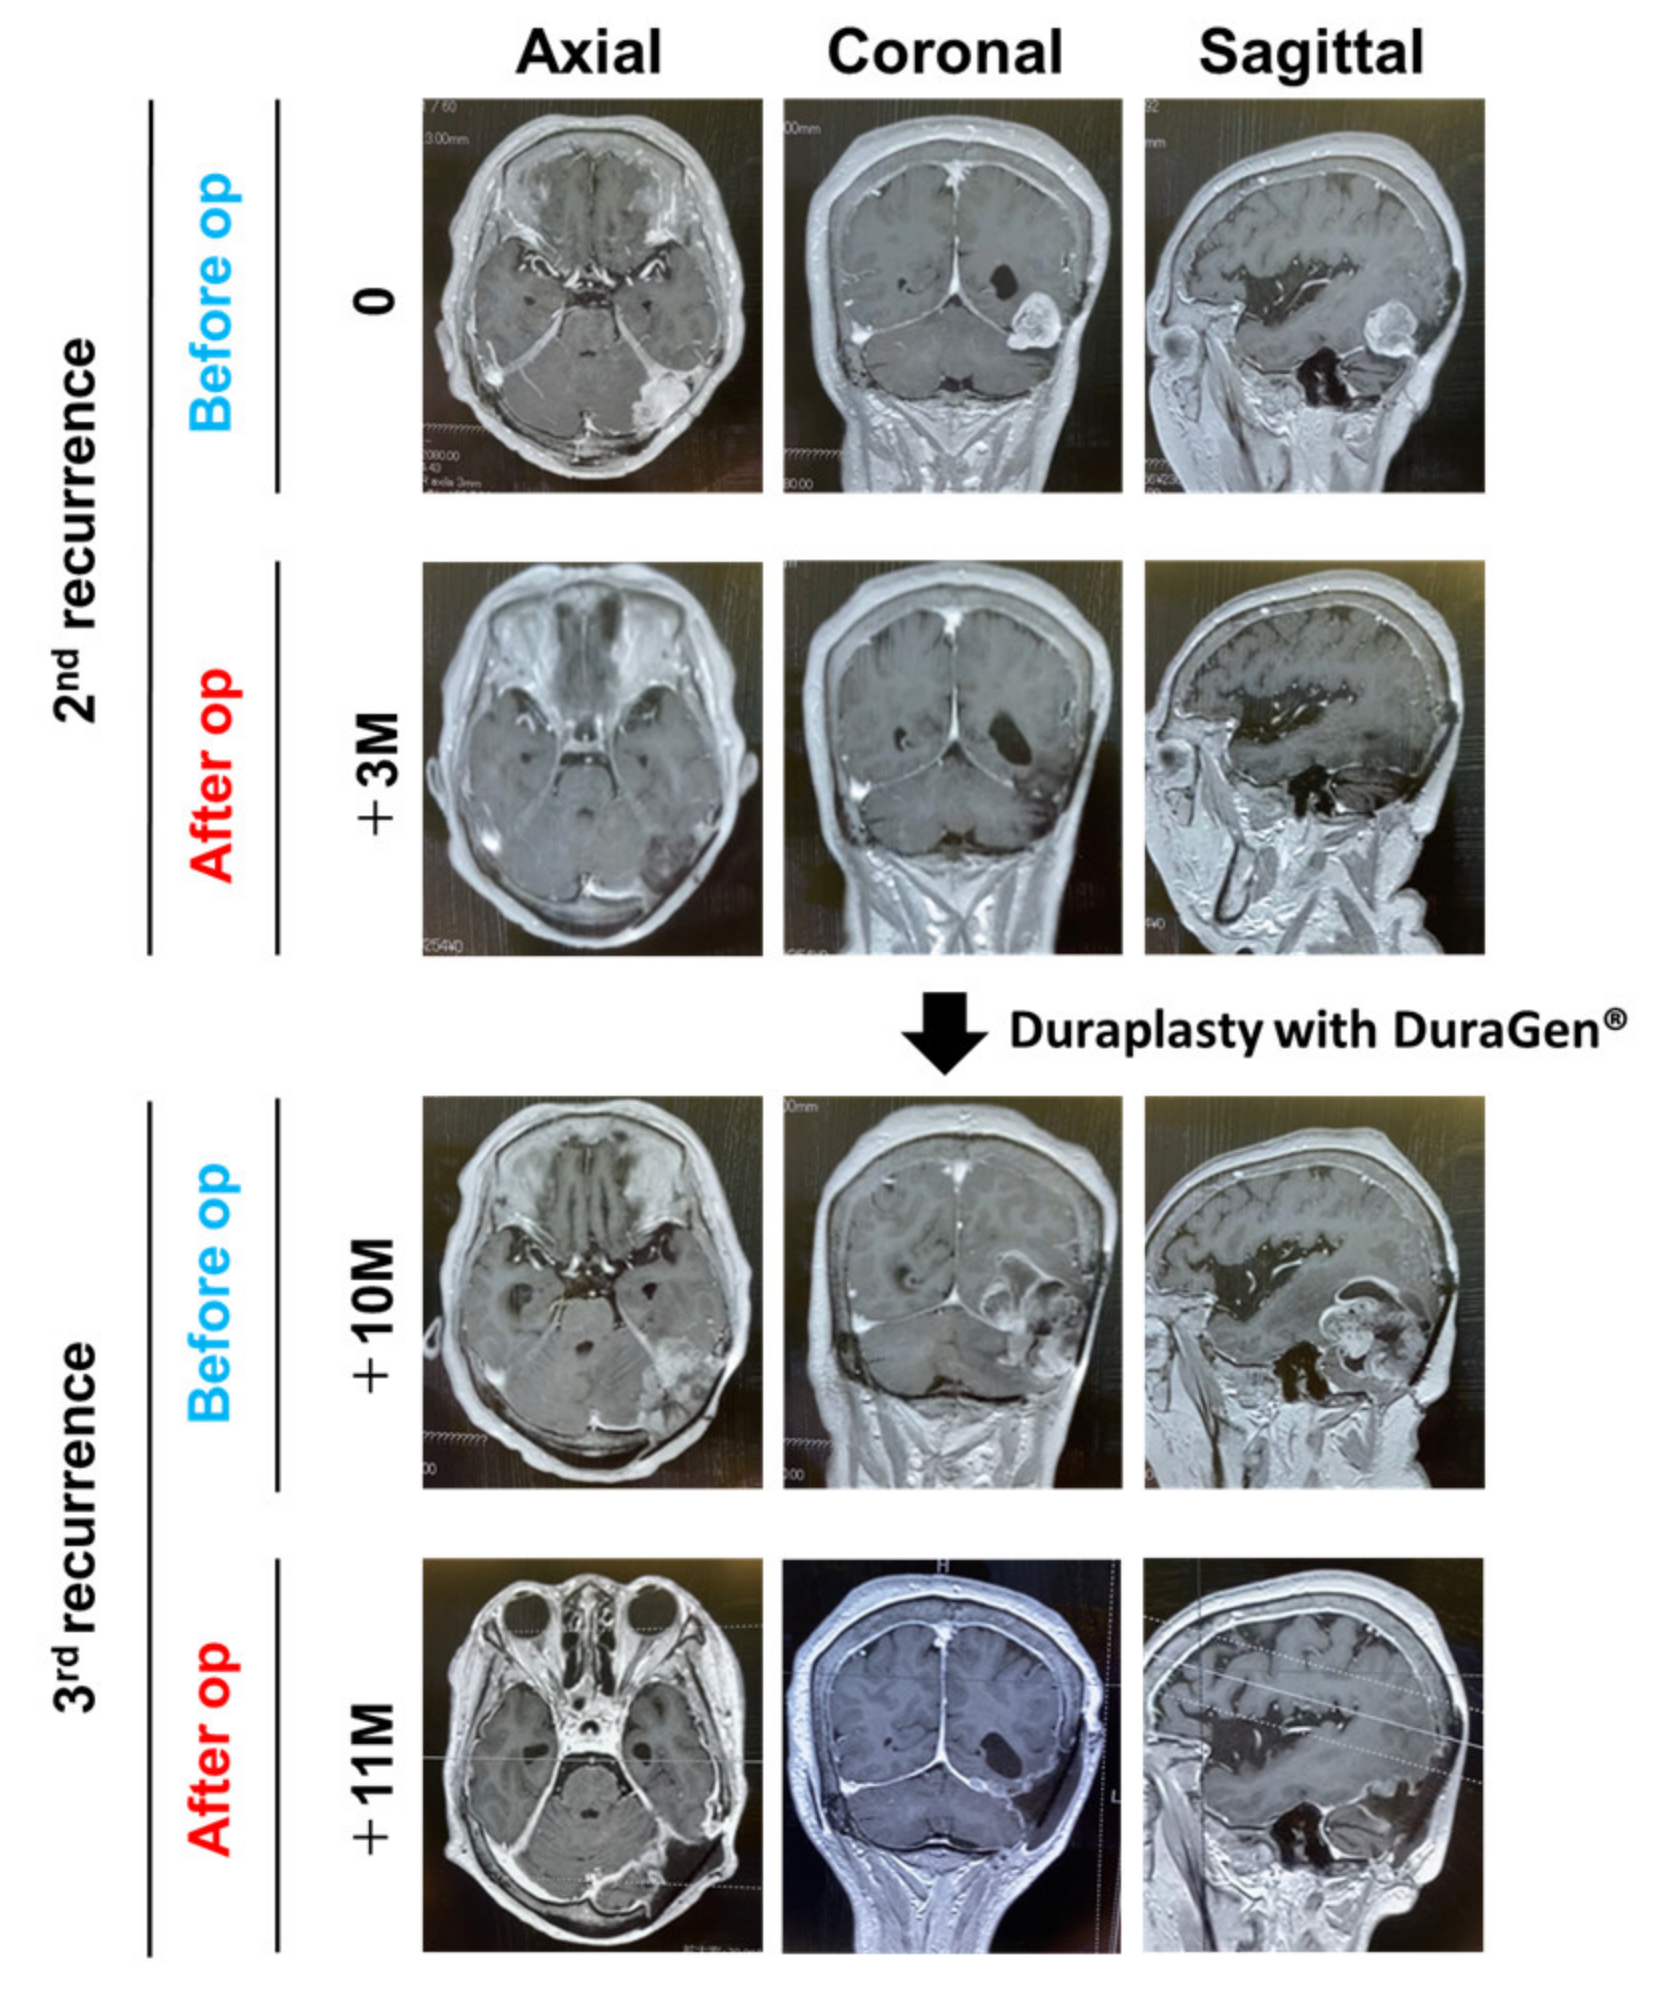

2. Case Presentation